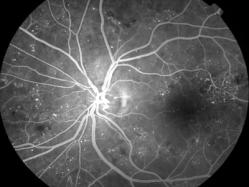

rétinopathie diabétique pré-proliférante

IM000002.jpg